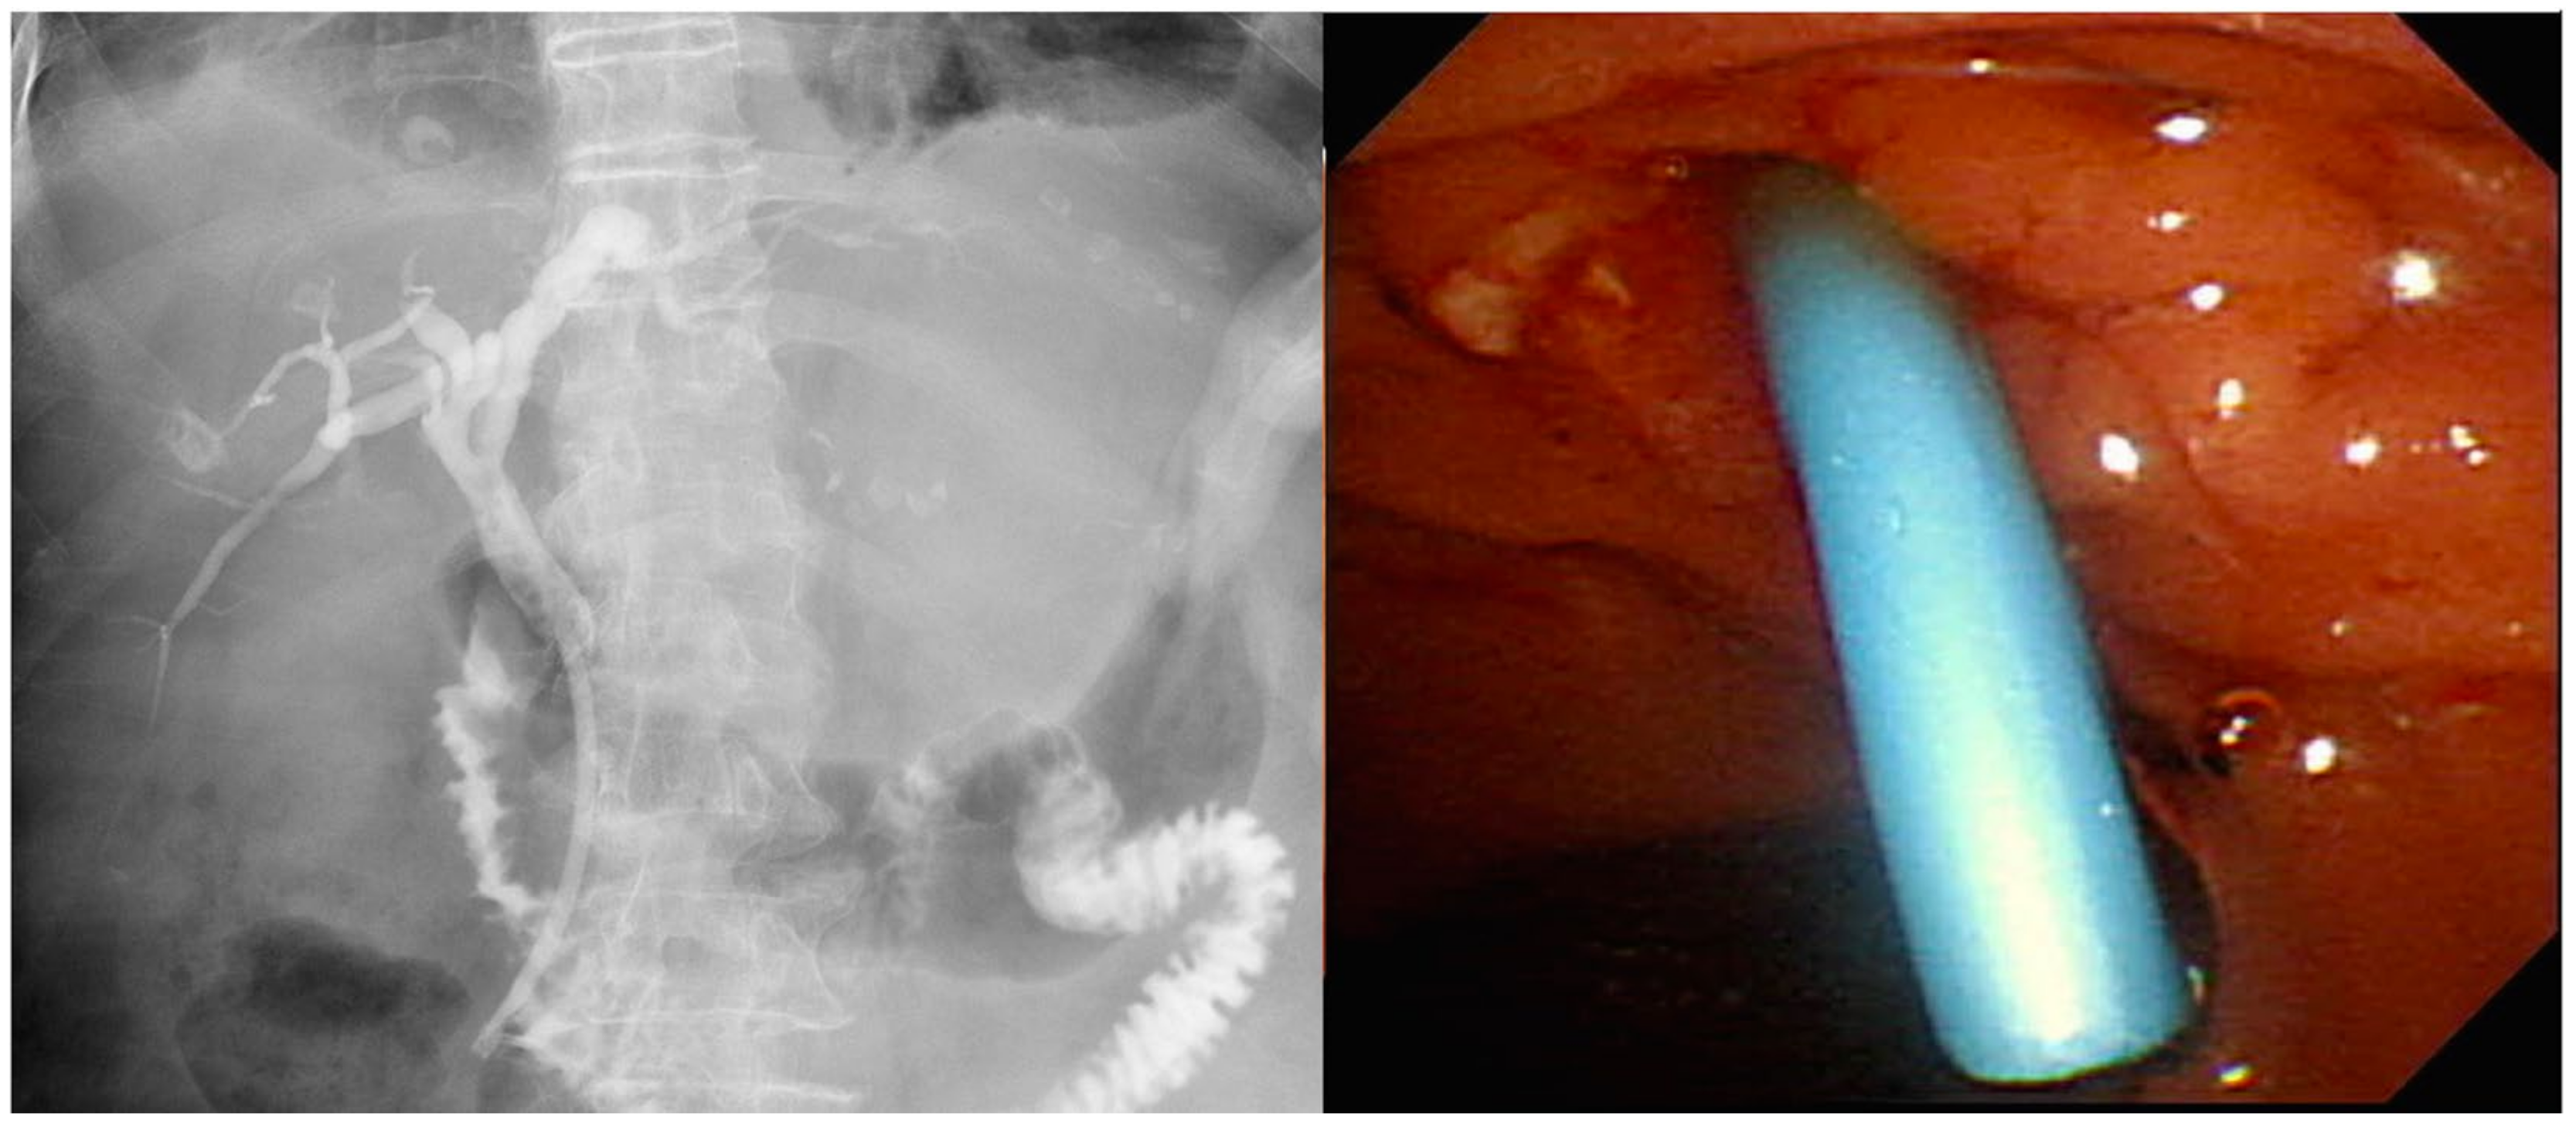

- Will, U.; Thieme, A.; Fueldner, F.; Gerlach, R.; Wanzar, I.; Meyer, F. Treatment of biliary obstruction in selected patients by endoscopic ultrasonography (EUS)-guided transluminal biliary drainage. Endoscopy 2007, 39, 292–295. [Google Scholar] [CrossRef]

- Park, D.H.; Song, T.J.; Eum, J.; Moon, S.H.; Lee, S.S.; Seo, D.W.; Lee, S.K.; Kim, M.H. EUS-guided hepaticogastrostomy with a fully covered metal stent as the biliary diversion technique for an occluded biliary metal stent after a failed ERCP (with videos). Gastrointest. Endosc. 2010, 71, 413–419. [Google Scholar] [CrossRef]

- Komaki, T.; Kitano, M.; Sakamoto, H.; Kudo, M. Endoscopic ultrasonography-guided biliary drainage: Evaluation of a choledochoduodenostomy technique. Pancreatology 2011, 11 (Suppl. 2), 47–51. [Google Scholar] [CrossRef]

- Dhir, V.; Itoi, T.; Khashab, M.A.; Park, D.H.; Yuen Bun Teoh, A.; Attam, R.; Messallam, A.; Varadarajulu, S.; Maydeo, A. Multicenter comparative evaluation of endoscopic placement of expandable metal stents for malignant distal common bile duct obstruction by ERCP or EUS-guided approach. Gastrointest. Endosc. 2015, 81, 913–923. [Google Scholar] [CrossRef]